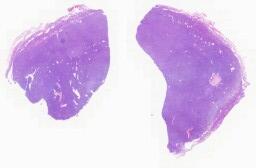

临床资料: 患者,男,74岁,2年前患者偶然发现右耳下1横指处一卵圆形肿物,直径约1.2cm,无痛不痒,活动度可,皮肤未见明显红肿破。2025-12-04浅表器官彩色多普勒超声检查(双涎腺及颈部淋巴结)检查所见:左侧腮腺,双侧颌下腺未见明显异常;右侧腮腺大小形态正常,下极见16*24mm不均匀低回声结节,边缘大致清楚,内回声低,不均匀,CDFI:见较丰富血流。其余三种回声均匀。检查意见:右侧腮腺下极不均匀低回声结节,混合瘤?

大体所见: 大体所见:灰白结节样物一枚,大小约2.5cm×2cm×1.3cm,表面略呈结节状,似有包膜,切面灰白实性质中,局灶呈胶冻样改变。

免疫组化: 无